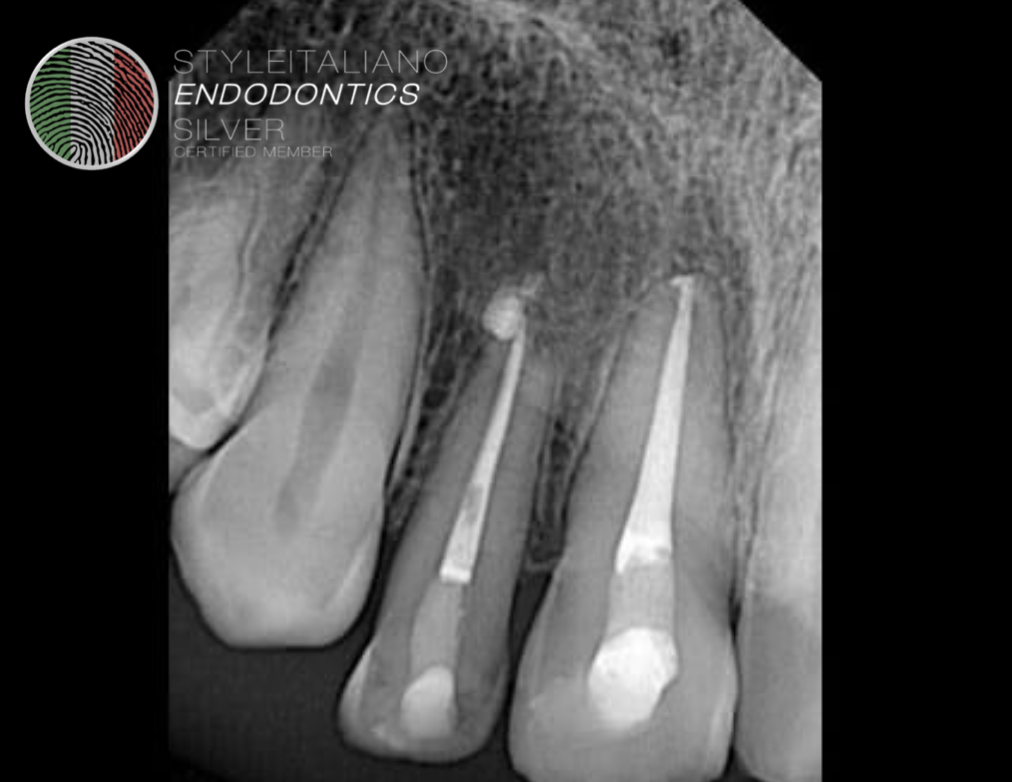

Fig. 3

Splint was removed after two weeks.. Patient was advised to come for endodontic treatment after two weeks.